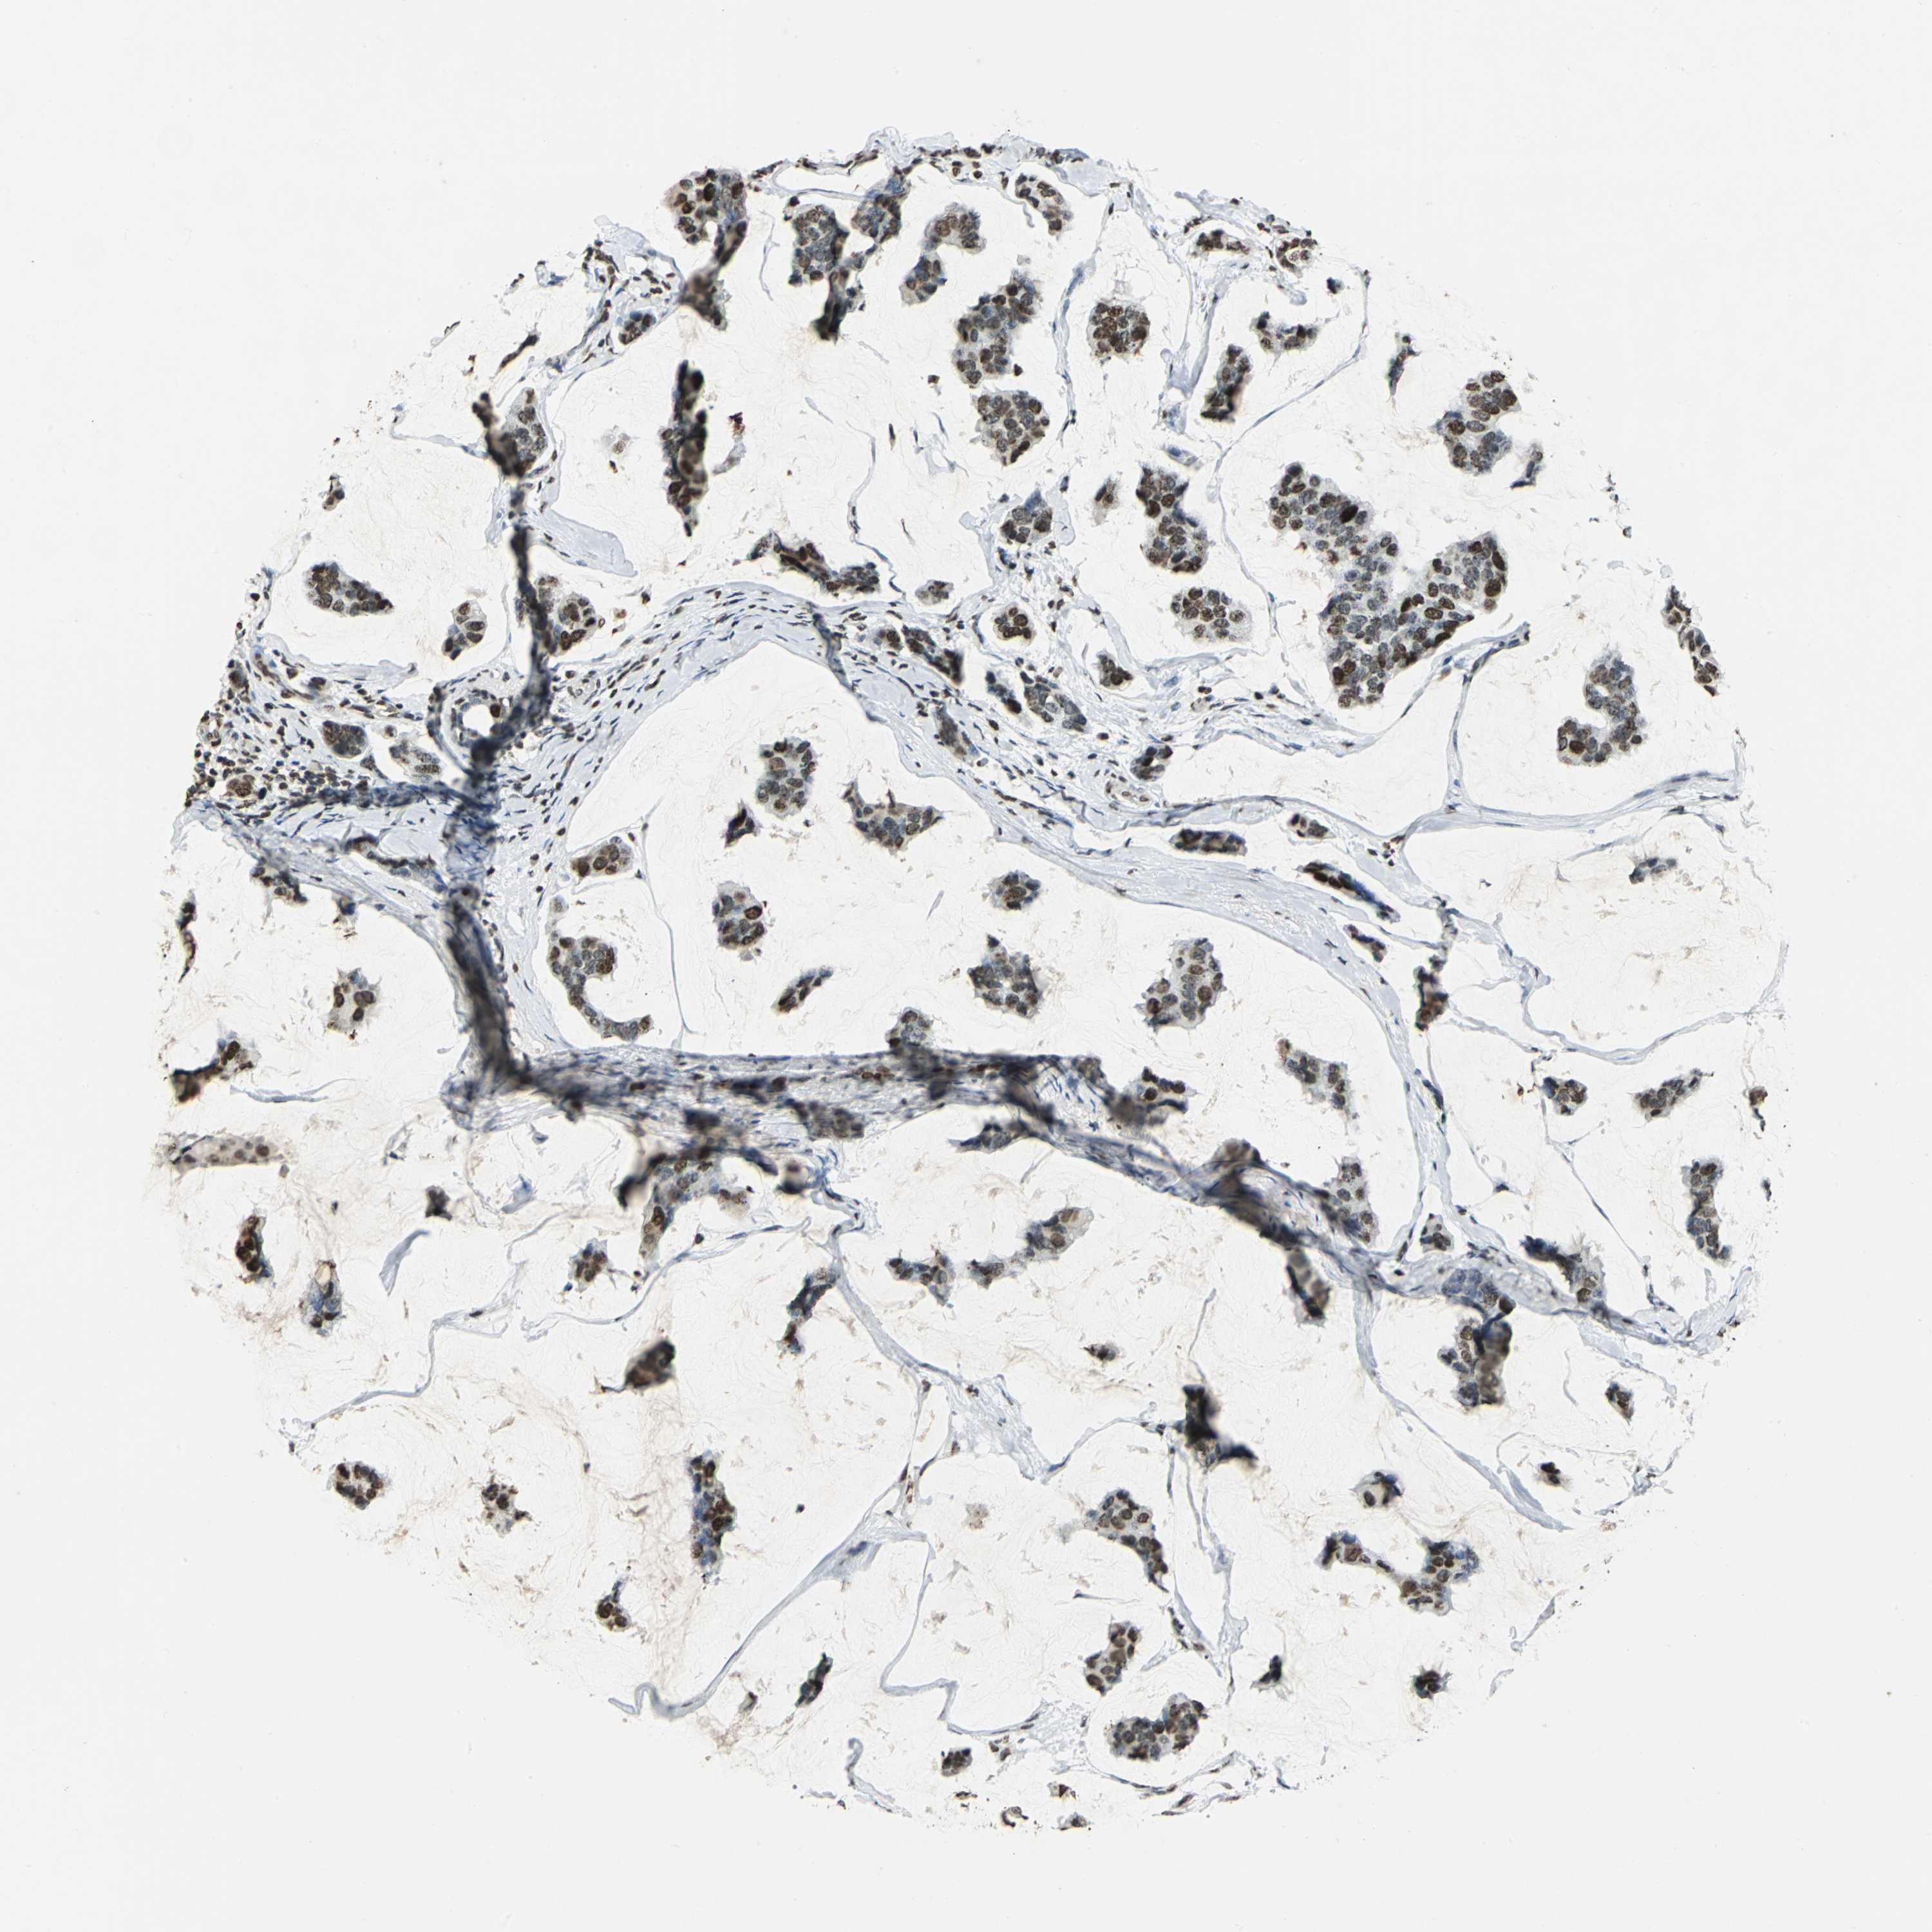

BRCA TCGA BRCA VALIDATION PROTEIN EXPRESSION

ANTIBODIES

AND

VALIDATION